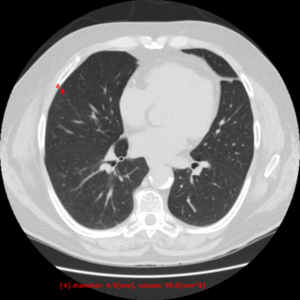

【EIRL Chest CTによる表示例】

(2) 低線量CT